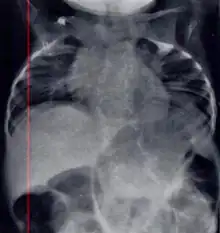

| Radiograph depicting typical skeletal features of Jarcho-Levin syndrome, subtype spondylothoracic dysplasia. Note fanlike configuration of the ribs, with extensive posterior fusion, along with multiple vertebral segmentation defects. | |

In contrast to STD, the subtype spondylocostal dysostosis, or SCD features intrinsic rib anomalies, in addition to vertebral anomalies. Intrinsic rib anomalies include defects such as bifurcation, broadening and fusion that are not directly related to the vertebral anomalies (such as in STD, where extensive posterior rib fusion occurs due to segmentation defects and extreme shortening of the thoracic vertebral column).[6] In both subtypes, the pulmonary restriction may result in pulmonary hypertension, and have other potential cardiac implications.[7]